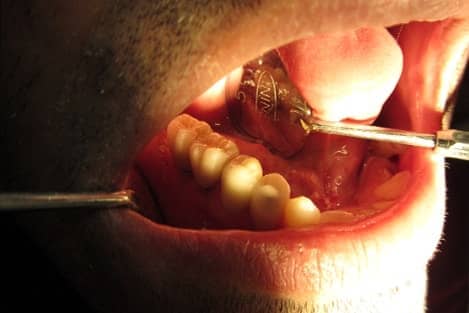

Post n Core